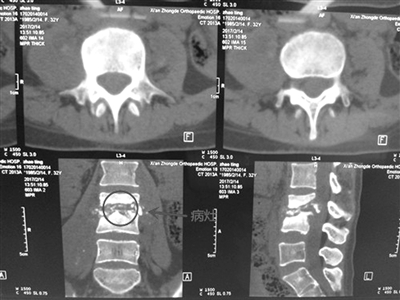

西安仲德骨科5楼脊柱外科32岁患者刘婷双腿疼痛半个月,患病以来一直以“腰椎间盘突出症”在当地医院进行治疗,理疗、服药后没有改善,疼痛蔓延至臀部,行走、久坐症状加重,精神、饮食受影响,体重骤降。来到仲德骨科医院,检查报告显示腰3、4椎体不同程度骨质破坏、对应椎间隙变窄、椎体旁软组织肿胀、密度不均,诊断为腰3、4椎体结核,伴马尾神经损伤。院长文益民教授组织科主任、手术麻醉科主治医生等进行会诊分析病情,讨论有关围手术前相关准备,决定施行腰椎侧前路腰3、4结合病灶清理植骨融合内固定术。

脊柱结核是结核杆菌全身感染的局部表现,应采取局部与系统兼顾的综合治疗,手术的目的在于清除病灶以及病灶破坏所造成的脊髓或神经受压、改善局部循环。文院长指出,手术后应严密观察,防止出现心脑血管病变等并发症,目前已为该患者成功实施手术,术后恢复良好。